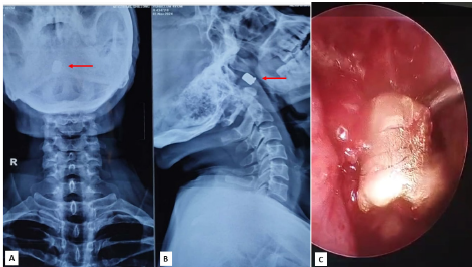

Background: Retained ballistic foreign bodies in anatomically intricate regions such as the nasopharynx or paranasal sinuses are exceptionally rare and pose diagnostic and therapeutic challenges.

Cases: We present two cases in 49-year-old males: Case 1 involved a bullet lodged in the posterior nasopharyngeal wall with multiple tooth fragments embedded in the tongue following intraoral gunshot trauma; Case 2 featured a metallic fragment retained in the left posterior ethmoid sinus after a self-inflicted nasal gunshot wound.

Management and Outcome: Both patients underwent emergency surgical intervention—open retrieval and tracheostomy for Case 1, endoscopic sinus surgery with septoplasty for Case 2—and recovered uneventfully.

Conclusion: These cases underscore the critical role of high resolution computed tomography, multidisciplinary planning, and tailored surgical approaches in successfully managing rare upper aerodigestive ballistic injuries.